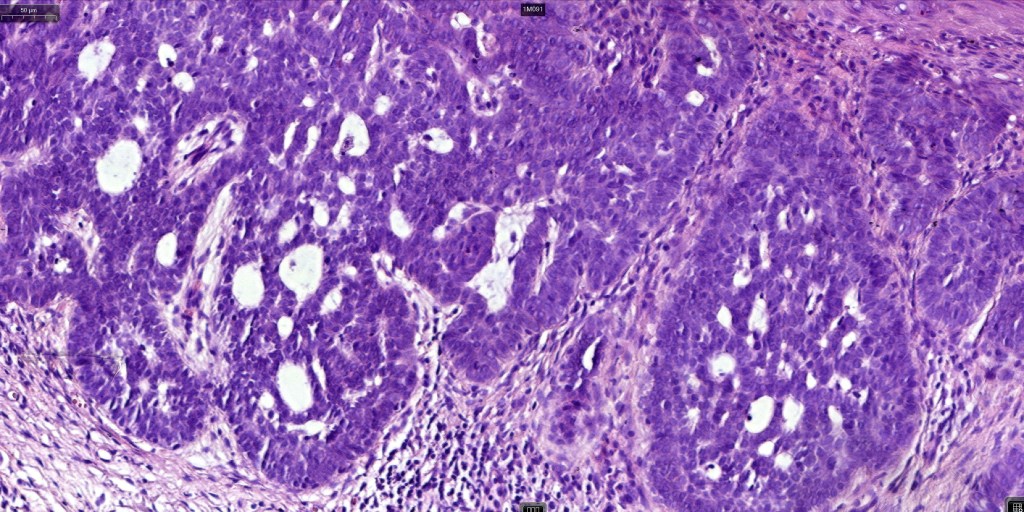

•The epithelial component is composed of uniform small, basophilic devoid of desmosomes

•Peripheral palisading

•Retraction artifact with stromal mucin

•Pseudoglandular appearance

•A wide variety of histological variants are possible including nodular, nodulocystic, ulcerative, superficial, micronodular, infiltrating/infiltrative, keratotic, basosquamous, pigmented, morpheaform, keloidal, clear-cell, signet-ring cell & granular cell variants, BCC with monster cells, BCC with metaplastic features, BCC with matricial differentiation, basomelanocytic tumor (see separate blog), BCC with thickened basement membrane, BCC with carcinoid-like nuclear palisading & these are illustrated below